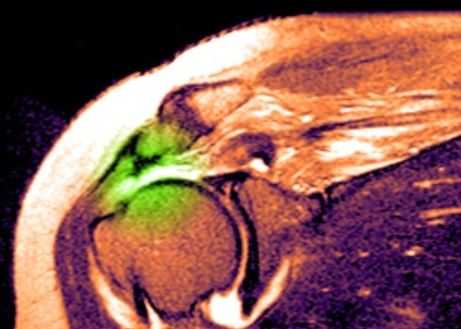

МРТ плечевого сустава. Т2-взвешенная корональная МРТ. Разрыв вращательной манжеты. Цветовая обработка изображения.

Анатомия плечевого сустава. Т1-зависимая МРТ в корональной плоскости. Обозначения: 1 -суставная (гленоидная) впадина, 2 - ключица, 3 -головка плечевой кости, 4 - подлопаточная мышца, 5 - дельтовидная мышца, 6 - длинная головка сухожилия двуглавой мышцы плеча, 7 - надостная мышца, 8 - трапецевидная мышца, 9 - сухожилие надостной мышцы, 10 - верхняя губа.